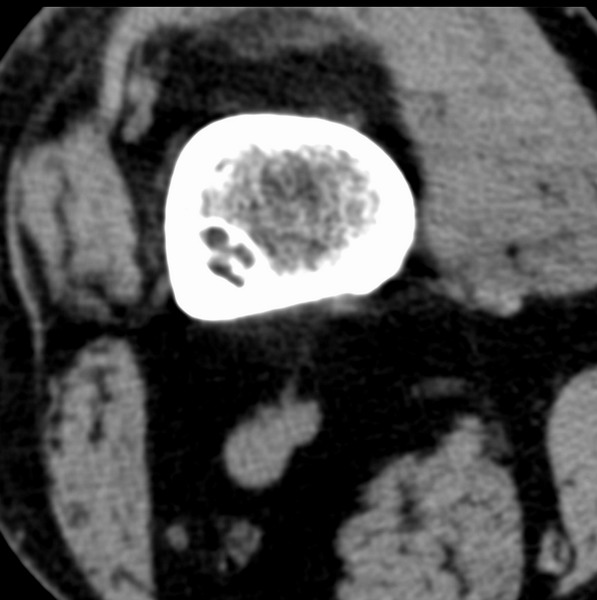

标题: CT21959:骨肿瘤请会诊。

右侧膝关节疼痛一月

男、48

股骨下段、胫骨上段。

1、股骨干骺端病变考虑干骺端纤维性皮质缺损愈后(非骨化性纤维瘤)改变,胫骨近端内生骨瘤(或干骺端纤维性皮质缺损愈后改变);

2、骨关节炎,骨质增生,股骨外侧髁退变性囊肿(关节面软骨下囊肿);

股骨干骺端病变考虑干骺端纤维性皮质缺损愈后(非骨化性纤维瘤)改变,胫骨近端内生骨瘤(或干骺端纤维性皮质缺损愈后改变);

多发内生软骨瘤!

股骨干骺端病变考虑非骨化性纤维瘤。

1、股骨干骺端病变考虑干骺端纤维性皮质缺损愈后(非骨化性纤维瘤)改变,胫骨近端内生骨瘤;